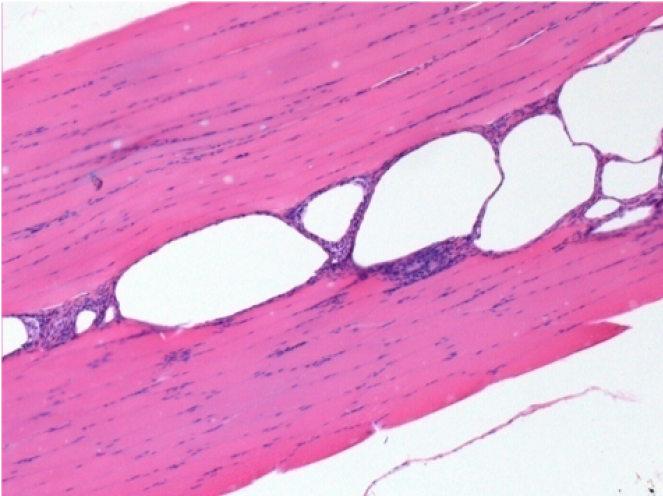

10 días después de la inyección de Endopeel 0,1 ml en el músculo pretibial derecho.

Aquí puede ver la formación de las vacuolas que están rodeadas de linfocitos. Las vacuolas son diferentes a la necrosis tisular. La presencia de linfocitos está relacionada con la permeabilidad de las membranas celulares.

07